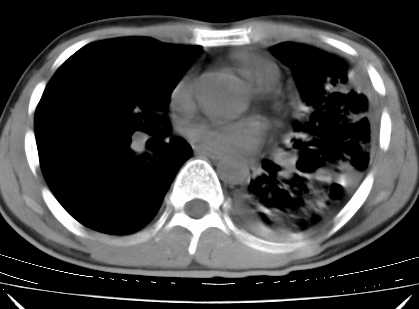

年龄?左侧胸腔中量积液,左下肺见有较多斑片状和大片状影,伴有支气管充气征,考虑:1、左下肺炎;2、结核。肿瘤可以基本排除。

考虑:1、左下肺结核左侧胸腔中量积液,心包积液纵隔肿大淋巴结.

考虑:1、左侧中量胸腔积液伴左肺下叶肺膨胀不全、炎症。

2、心包积液。

左下肺见有较多斑片状和大片状影,支气管通畅,左侧胸腔积液,考虑:左下肺炎伴胸腔积液

左侧中量胸腔积液伴左肺下叶肺膨胀不全、上肺外围多个小囊样腺泡样病灶。考虑化脓炎症。

心包积液没有,纵隔积液。

纵隔肿大淋巴结不明显。

1、左侧中量胸腔积液伴左肺下叶肺膨胀不全、。

3 无纵隔肿大淋巴结.

左肺舌叶及下叶见斑片状,大片状高密度影并相应处胸膜及心包不规则增厚,左肺下叶膨胀不全。右肺未见异常,双肺段以上支气管通畅。纵隔左移,其内未见明显肿大淋巴结。左侧胸腔积液。

1.考虑:左肺化脓性炎症。2.左侧胸腔积液(中等量)。3.心包炎症。